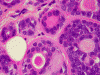

Panel A is a low-magnification photo taken at the edge of the tumor that shows tumor invasion into the surrounding salivary gland tissue. Well formed cribiform arrangment by tumor cells are show in panel B, C, and D; a fibrous stroma can be well appreciated in these photographs. Eosinophilic basement membrane like material can be well recognized in panel E; mucoid material containing microcysts are well illustrated in panel D and F. The myoepithelial component are recognized by strong immunoreactivity for calponin and smooth muscle actin (SMA) in panel G an H; note that the luminal epithelial cells do not have such immunoreactivity. Strong immunoreactivity of the tumor cells for pancytokeratin are well demonstrated in panel I

The histologic features are well illustrated in this case. In general, ADCC is a malignant tumor that is clearly invasive at macroscopic and microscopic levels. Grossly, they are usually fibrous mass with invasion into the surrounding tissue. The stroma of ADCC is typically fibrotic. The common histologic patterns are the cribiform pattern, tubular pattern and solid pattern. The less common pattern are the spindle cell pattern, trabecular pattern and solid type with comedo-type necrosis. Common histologic features are cribriform or microcystic architecture with relatively uniform cells, with small, hyperchromatic nuclei, scant cytoplasm, somewhat nulcear molding and indistinct cytoplasmic border. These cells are considered as myoepithelial differentiation.  A second cell type can be recognized as somewhat larger, with more abundant cytoplasm and less dense nuclear chromatin. These cells are thought to represent ductal epithelial cells. The ductal cells give rise to real tubular structures that contain bluish mucoid material; these cells are immunoreactive for carcinoembryonic antigen (CEA), epithelial membrane antige  (EMA), keratin, and S-100 protein. The myoepithelial cells may arrange in solid sheets and also give rise to microscystic structures containing hyalinized eosinophilic basement membrane-like material. They bear immunoreactivity for calponin, muscle specific actin, and low molecular weight cytokeratin. They are also positive for S-100 protein but are usually less strong than the ductal cells in the same tumor. Many ADCC also express C-kit (CD117) 2, especially in solid type. PAS (+) basement membrane-like material is seen in the pseudocyts and mucin in the true ducts. Perineural invasion is the rule. The tumor cells are highly proliferative and a Ki-67 labeling index over 20% is not uncommon.